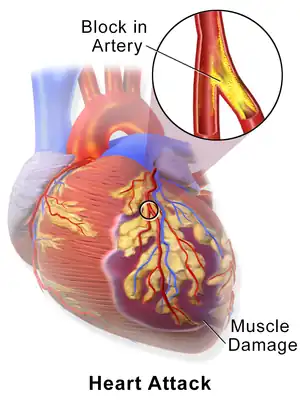

| A myocardial infarction occurs when an atherosclerotic plaque slowly builds up in the inner lining of a coronary artery and then suddenly ruptures, causing catastrophic thrombus formation, totally occluding the artery and preventing blood flow downstream. | |

The most common cause of a myocardial infarction is the rupture of an atherosclerotic plaque on an artery supplying heart muscle.[38][70] Plaques can become unstable, rupture, and additionally promote the formation of a blood clot that blocks the artery; this can occur in minutes. Blockage of an artery can lead to tissue death in tissue being supplied by that artery.[71] Atherosclerotic plaques are often present for decades before they result in symptoms.[71]

The gradual buildup of cholesterol and fibrous tissue in plaques in the wall of the coronary arteries or other arteries, typically over decades, is termed atherosclerosis.[72] Atherosclerosis is characterized by progressive inflammation of the walls of the arteries.[71] Inflammatory cells, particularly macrophages, move into affected arterial walls. Over time, they become laden with cholesterol products, particularly LDL, and become foam cells. A cholesterol core forms as foam cells die. In response to growth factors secreted by macrophages, smooth muscle and other cells move into the plaque and act to stabilize it. A stable plaque may have a thick fibrous cap with calcification. If there is ongoing inflammation, the cap may be thin or ulcerate. Exposed to the pressure associated with blood flow, plaques, especially those with a thin lining, may rupture and trigger the formation of a blood clot (thrombus).[71] The cholesterol crystals have been associated with plaque rupture through mechanical injury and inflammation.[73]